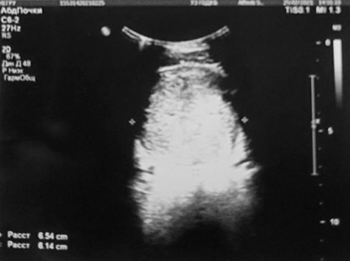

УЗИ почек и надпочечников: УЗ-картина объемного образования мочевого пузыря, забрюшинного пространства (гематома (?) опухоль (?) абсцесс (?)) (см. рис. 2);

Рисунок 2. Результаты УЗИ почек и надпочечников.